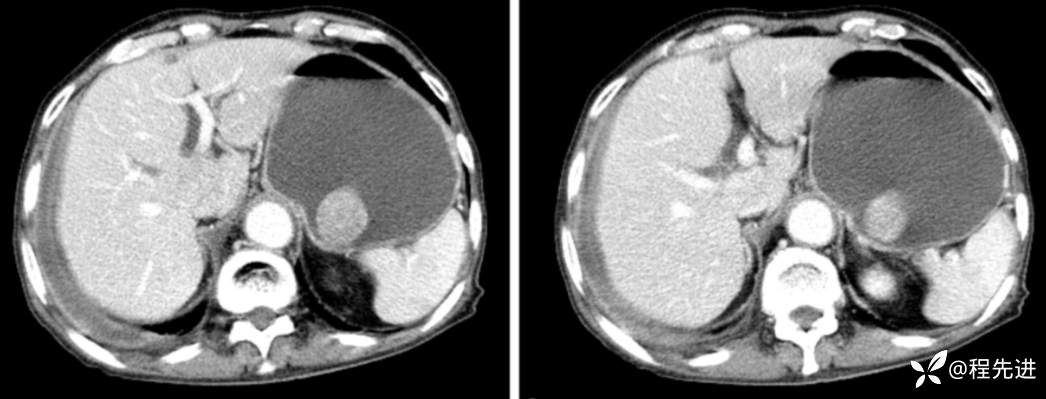

动脉期

门脉期